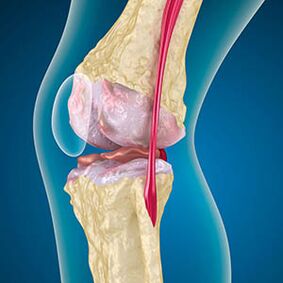

Artroz ile, kemiklerin kenarlarını kaplayan kıkırdak aşınma veya tamamen yoktur. Hasarlı doku bir ağrı kaynağı değildir, çünkü reseptörleri yoktur. Yakındaki yapılarda iltihaplanma karakteristik semptomlara neden olur.

Vücut hasarlı dokuların yenilenmesini sürdürür, ancak kıkırdak düzensiz olarak büyür. Sonuç olarak, eklemin diğer unsurlarını yaralayan düzensizlikler oluşur. Osteofitlerin doğası, pürüzsüz eklem kıkırdağı için tazminat ile açıklanmaktadır. Başka bir versiyon, "Spurs" in büyümesinin Kas zayıflaması nedeniyle eklemi medial veya yanal stabilize etme girişimi ile ilişkilidir.

Artrozun ilk aşamasındakazayla tespit edilen, kemik mahmuzlarında hafif bir artış meydana gelir. Büyümeler, eklemin en büyük istikrarsızlığındaki yerlerde ortaya çıkar. Tipik olarak, hastalar hareket sırasında nadiren ağrı veya rahatsızlık yaşarlar.

Artrozun ikinci aşaması kolay kabul edilir. Radyografi önemli kemik mahmuzları ortaya çıkarır, ancak kıkırdak etkilenmez. Sinovyal sıvı miktarı azalır, ancak uzun yürüme ve koşmadan sonra ağrı belirtileri, eklemde sertlik ve büküldüğünde ve dizlerin üzerindeki pozisyonda görülür.